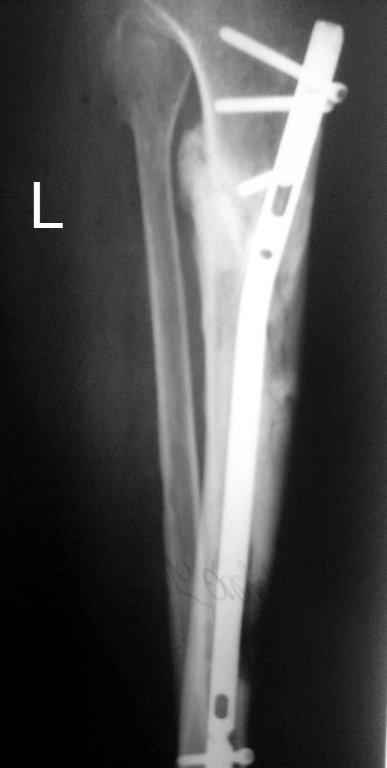

В июне 2009 года, при рассверливании канала произошел ожог передней стенки ББК.

Итак, в настоящий момент больной пришел к нам с полной нагрузкой на оперированную конечность и с такой картиной (см. приложение). Участок мягких тканей с передней стенкой нижней трети ББК, выгнил и представляет дефект 2×2,5 см. На перевязке - циркулярный(?) некроз костной трубки.

1 этап - резекция tibia + косая остеотомия fibula + «острое» укорочение + IM цемент-гвоздь с а/б + beads.

2 этап (по заживлению раны) – удаление цемент-гвоздя + (LATN) Lengthening and Then Nailing.